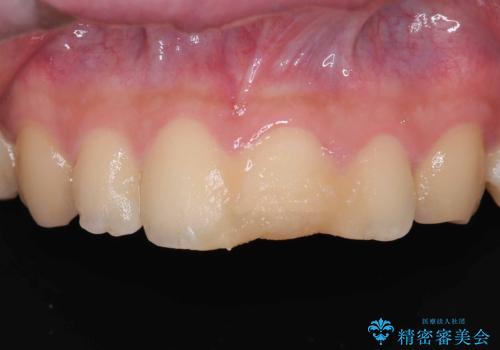

神経の状態が良好に保たれていることを確認した後、オールセラミッククラウンによる審美修復を行いました。

なお、最終補綴前にはオフィスホワイトニングを実施し、より自然で明るい仕上がりを得ることができました。

- 税込209,000円(VPT歯髄保存療法44,000円+仮歯11,000円+オールセラミッククランスペシャル154,000円)費用は治療当時の料金となります